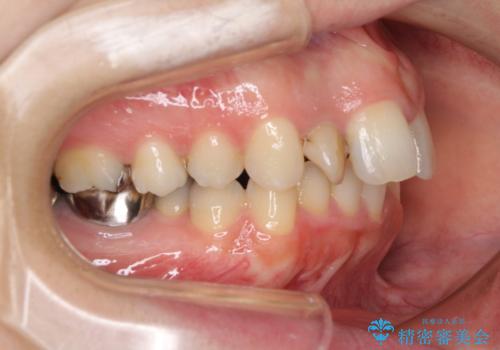

- 上顎前歯が叢生により前方に出ている状態や、全体的なむし歯を気にして来院された患者様です。

全体的にむし歯や欠損が多く、矯正治療とは別に処置が多く必要な口腔内でした。

口元の突出感を改善するために小臼歯4本を抜歯することとしましたが、左下は大臼歯が欠損していたため、そのスペースを活用し、小臼歯を3本抜歯して治療を行うこととしました。